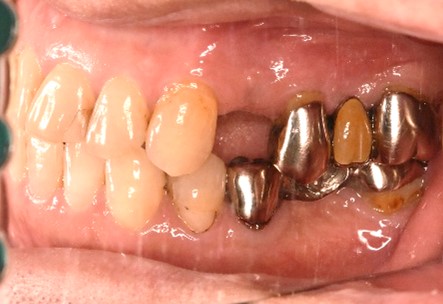

男性Eさん 80代(インプラント)

主訴

左上2本が動いていて、噛むと痛みがある。歯がないところに歯を入れたい。

治療内容

左上第二小臼歯と第一大臼歯の歯根が破折していたため、保存することができず抜歯しました。第一小臼歯は、すでにありませんでしたので、2本抜歯後3本欠損のところにインプラントを2本埋入しました。

所感

2006年10月に右下と左下の欠損部分にインプラント治療をしました。今回も左上の歯を失ったところは、インプラント治療を希望されました。

Before

※赤丸は、歯根が破折していたため抜歯しました

※黄色丸は、2006年10月に埋入したインプラント